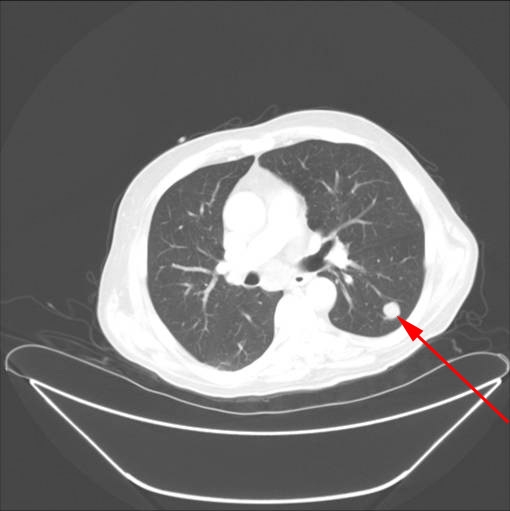

Die meisten Zysten entstehen in der Leber (70 %), die Lunge ist zu 20-30 % betroffen Mehr als 20 Prozent der über 60-Jährigen haben eine oder mehrere Zysten an den Nieren. In der Computertomographie kann hingegen die Größe, Form, Zahl und Verteilung der Zysten beurteilt werden.

Zyste An Der Lunge Pregnancy Informations. [Folliculin]-Gens auf Chromosom 17p11), welche zu charakteristischen Hautveränderungen (Fibrofollikulomata) im Gesicht und zu charakteristischen zystischen Veränderungen in den Lungen führt Lungenzysten weisen meist eine < 2 mm dünne, fibröse oder epitheliale Wand auf